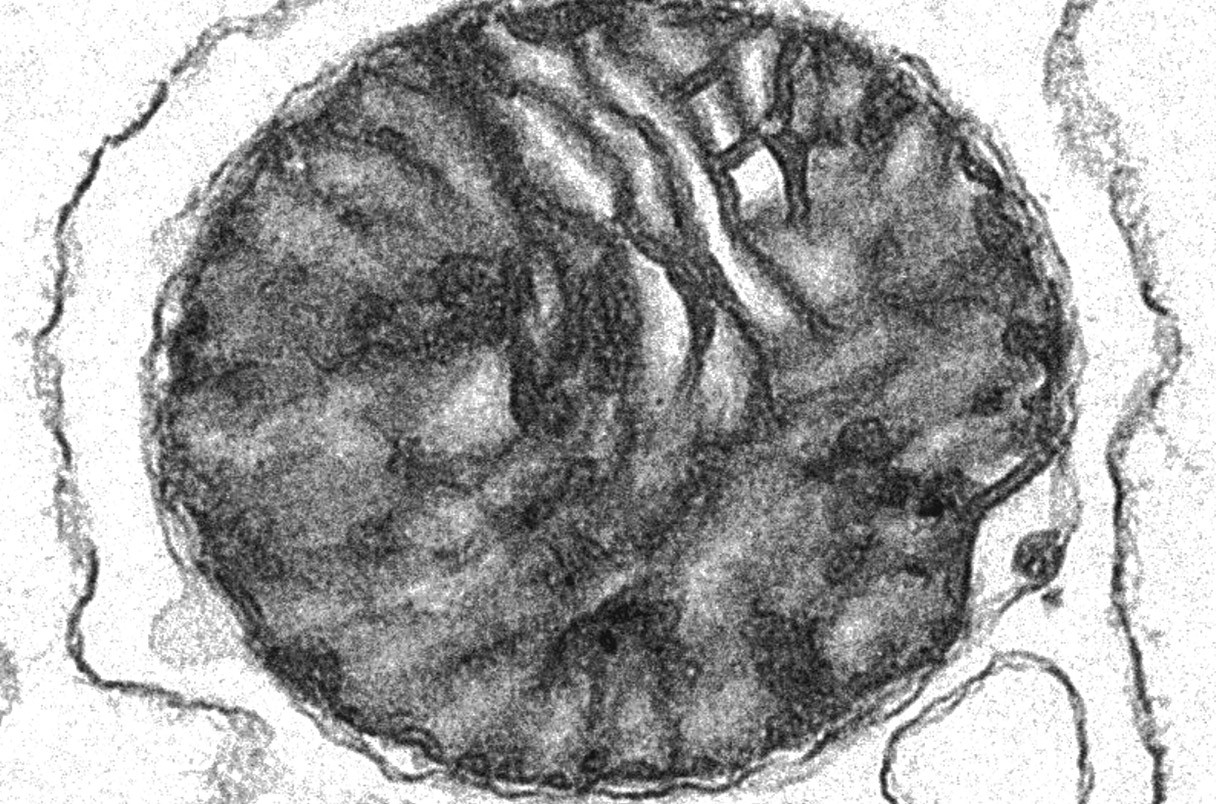

7 Mitochondria packaged in blood cell membranes improve disease symptoms in mice

Tiny capsules can deliver healthy organelles into animals with Parkinson’s-like and other mitochondria-linked disorders